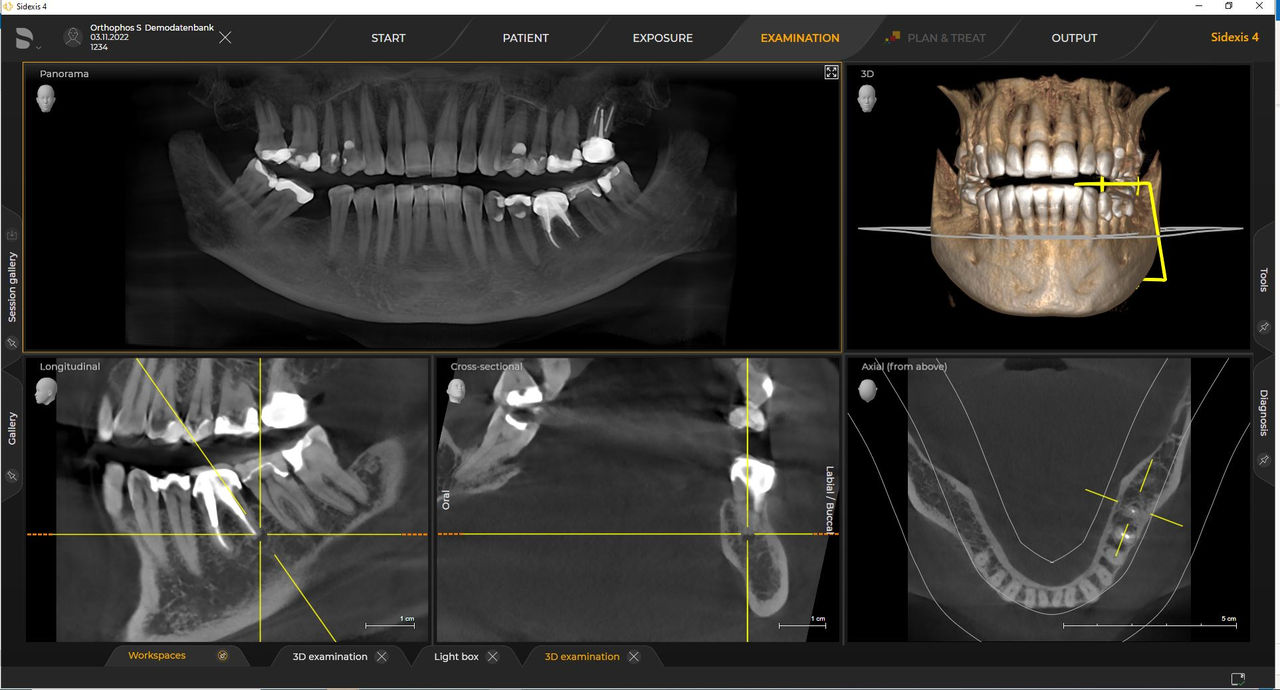

De vereisten volgen die voor beeldverwerkingssoftware Sidexis 4 en Orthophos S. Raadpleeg voor meer informatie Sidexis 4-systeemvereisten en Orthophos S-installatievereisten.

Dentsply Sirona-röntgeneenheden werken uitsluitend met Sidexis 4. Toch is de gegevensmigratie van Sidexis XG naar Sidexis 4 heel eenvoudig. Sidexis 4 zorgt voor een volledige digitale ervaring met de nieuwste tools